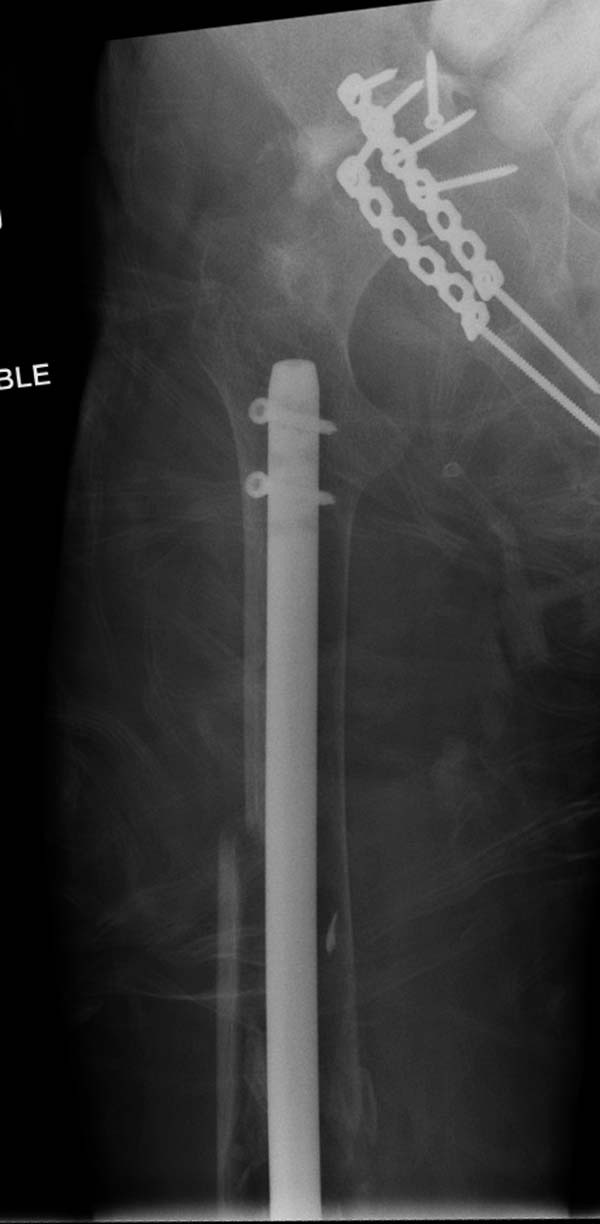

остаться до конца лечения, начал изучать язык... Для облегчения

транспортировки на второй день после поступления правая сторона была

фиксирована ретроградным гвоздем.

Теперь по серьезному. Учитывая качество кости и низкий гемоглобин,

периодический гемодиализ и воодушевленный результатом выступлении

Челнокова, вместо пластины решил попробовать гвоздь. Но жесткие FDА

Гвоздь из ретроградного гвоздя DePuy в 15 мм получился немного тоньше,

чем у Российских коллег.

А так вроде первый американский опыт прошел удачно. У больного низкий

гемоглобин, который подправили во время операции переливанием крови.

надеюсь, контрагированные мышцы сохранит длину конечности. Контрольный

снимок показал устойчивую фиксацию.